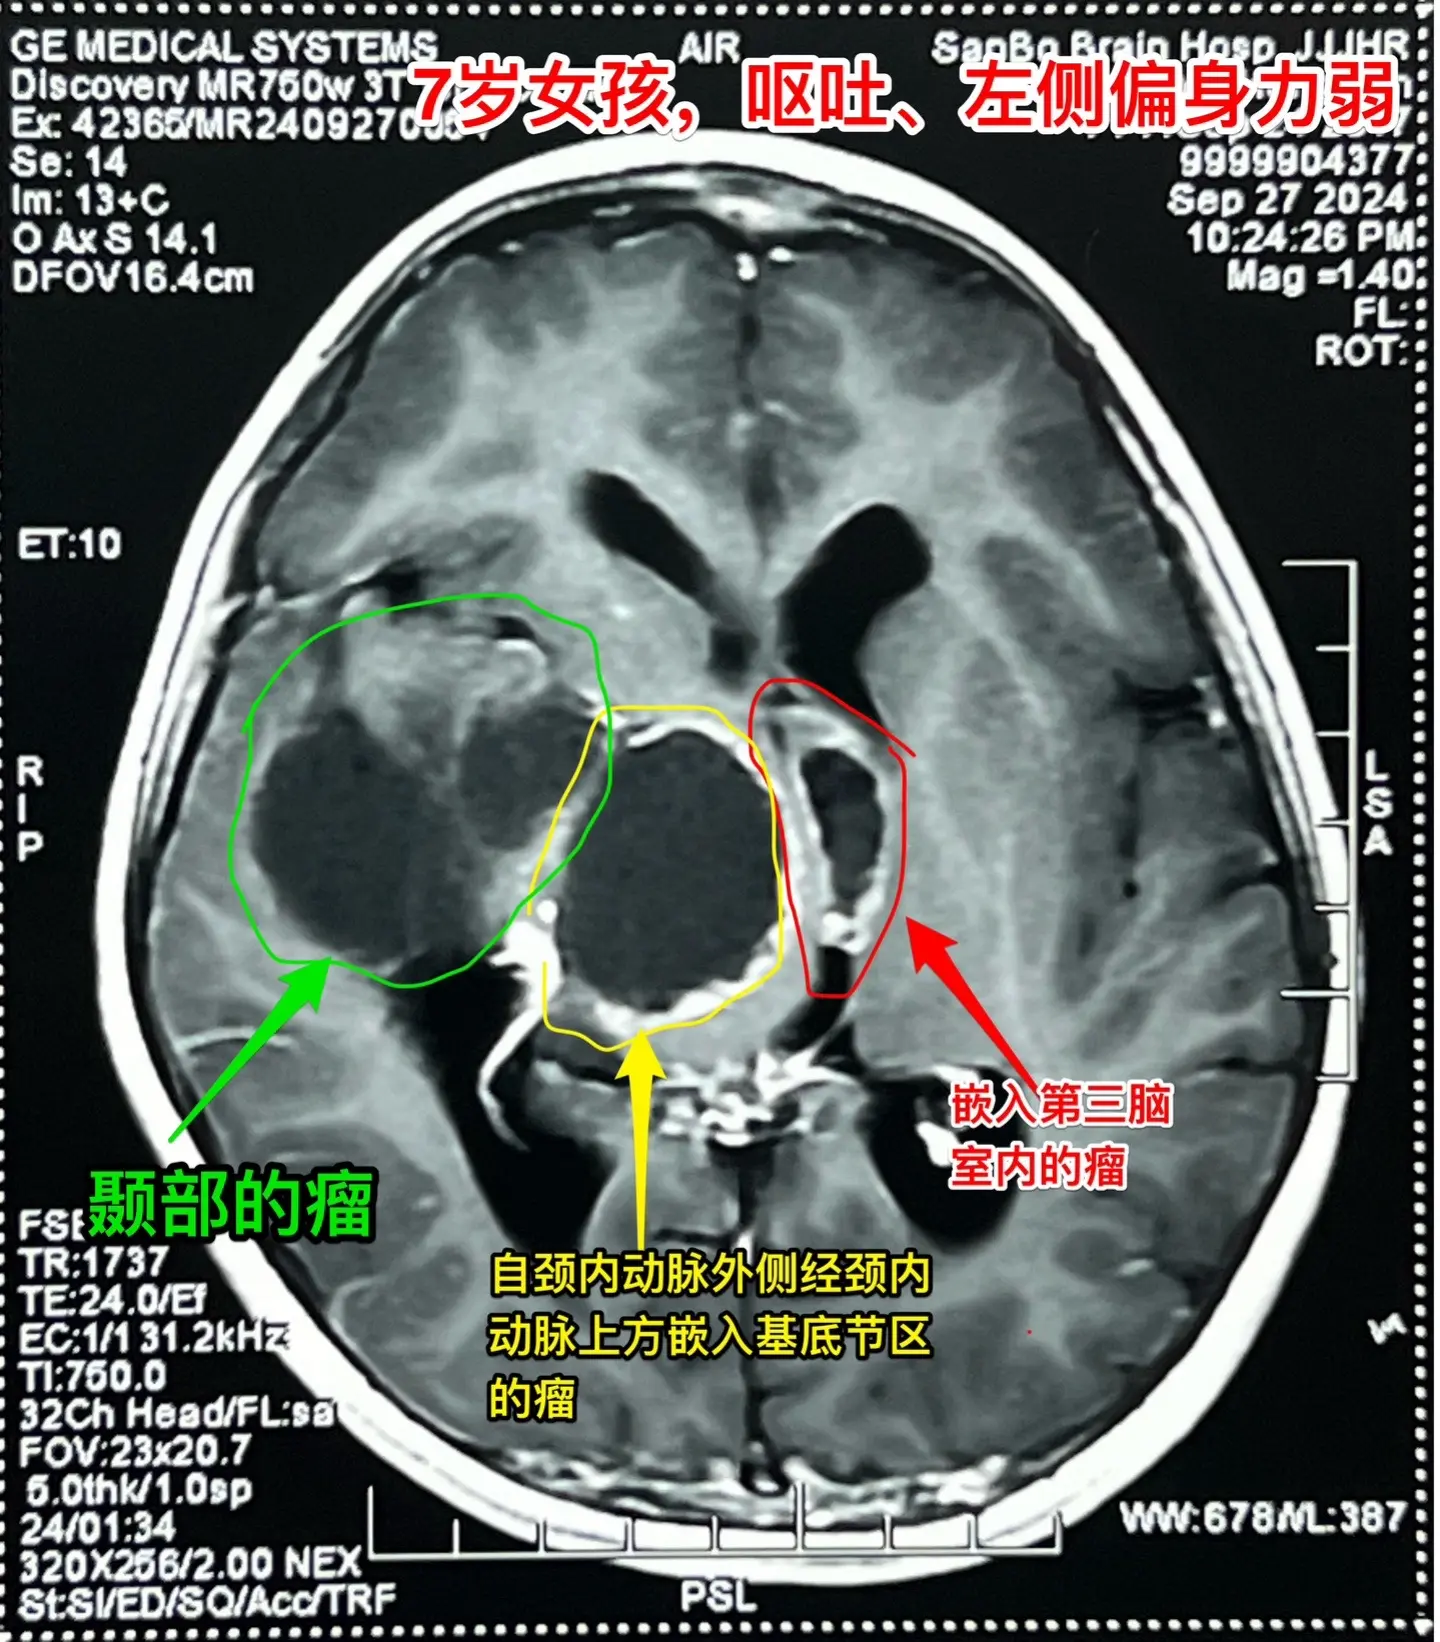

漳州市女孩子脑部长了巨大的颅咽管瘤。7岁漳州市女孩子,入院前两个月经常...